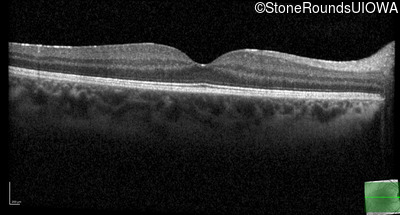

Optical Coherence Tomography - Right - 20/25

Exemplar / OCT Stack